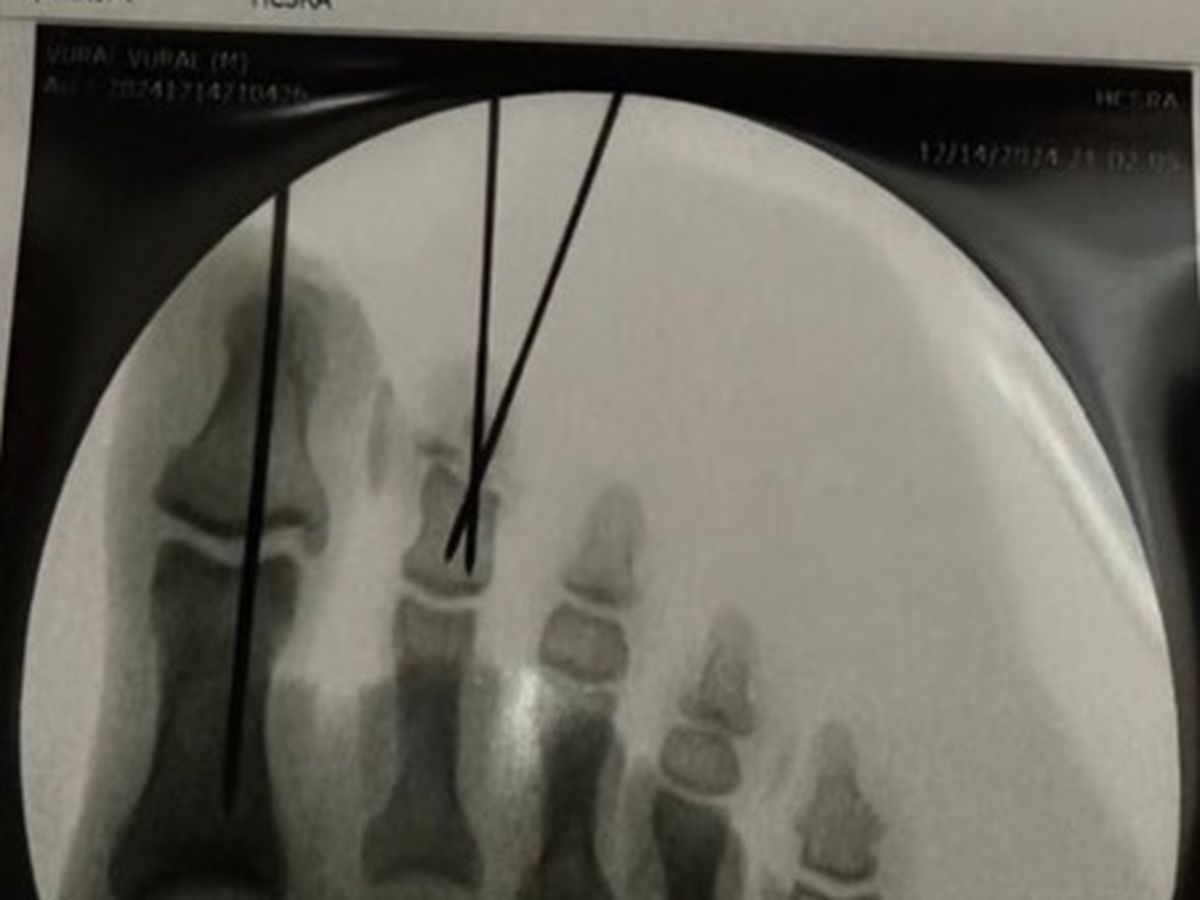

Currently I’m in the hospital recovering from the surgery and I will have metal pins sticking out of my toes to keep them together for the next month, while I’m on crutches.

Yesterday I had an accident while trimming some trees with a chainsaw and severely damaged my big toe and 2nd toe. Having gone through emergency surgery, it still remains to be seen if the 2nd toe will need to be partially amputated if there isn’t enough circulation.

UPDATE: I am now home, changing bandages around the pins in the big toe and the 2nd toe… on Wednesday we find out for certain if the 2nd toe is salvageable or will need to be partially amputated. Doctor has a positive outlook as he sees circulation at the part that was severed.

Today at a follow-up appointment the orthopedic surgeon made the decision that a joint amputation will NOT be necessary! This is a BiG WiN as that would’ve affected balance and function!